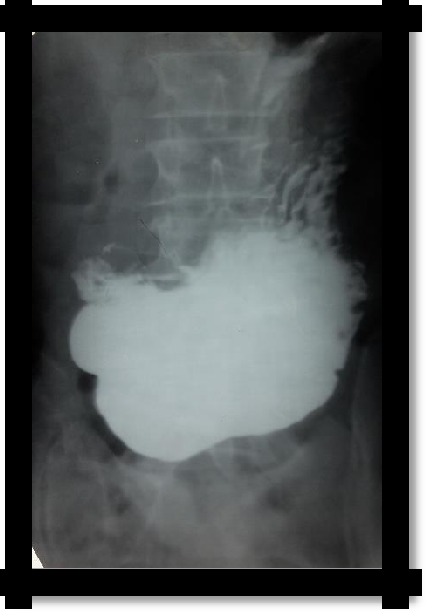

1. Radiological - the evacuation of the contrast mass from the stomach to the duodenum is slow, but quickly occurs after exposure to atropine, (compensated stenosis), does not change after pharmacological treatment with decompensated stenosis, gastric tetany syndrome (chlorohydropenic) develops.

1. EFGDS - narrowing of the output section of the stomach

2. An increase in the remainder of an empty stomach (more than 200 ml)

Pic 4.2 Pyloric stenosis (enlarged stomach in the pelvis)